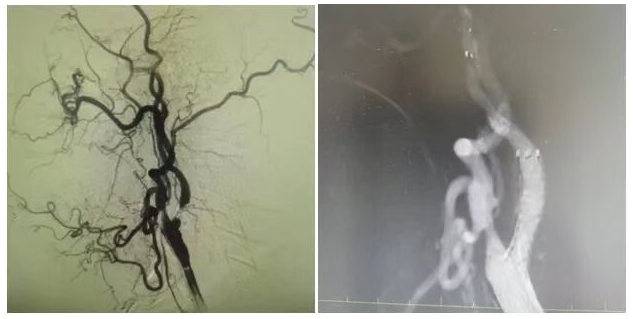

為明確病因,團(tuán)隊(duì)為姜大爺安排針對(duì)性檢查:頭顱 MRI 彌散成像顯示左側(cè)大腦半球有分水嶺性腦梗死,提示腦組織缺血損傷,頸部 MRA 檢查發(fā)現(xiàn)左側(cè)頸內(nèi)動(dòng)脈起始處重度狹窄,血流信號(hào)減弱。隨后的 DSA(數(shù)字減影血管造影)檢查進(jìn)一步明確,左側(cè)頸內(nèi)動(dòng)脈起始處狹窄程度超 90%,呈 “閉塞前改變”,血流受阻導(dǎo)致左側(cè)大腦半球供血不足,進(jìn)而引發(fā)腦梗死與抽搐。

手術(shù)當(dāng)天,丁金明主任親自操刀,團(tuán)隊(duì)默契配合:在姜大爺右側(cè)腹股溝穿刺股動(dòng)脈置入動(dòng)脈鞘,沿鞘送導(dǎo)絲和導(dǎo)管,在 DSA 引導(dǎo)下穿過狹窄部位,用球囊預(yù)擴(kuò)張后,精準(zhǔn)釋放頸動(dòng)脈支架。術(shù)后 DSA 顯示左側(cè)頸內(nèi)動(dòng)脈血流通暢,狹窄解除。手術(shù)歷時(shí) 1 小時(shí),姜大爺生命體征平穩(wěn),無(wú)并發(fā)癥。